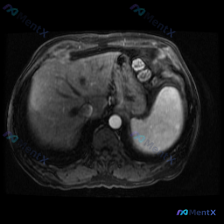

整理了一份有点意思的读片分析,核心是“关注点错位”——临床问的是脾脏病变,但影像的真正异常在肝脏。 一、先看影像基础信息 - 序列:腹部MRI轴位T1加权像 - 覆盖范围:上腹部(肝左/右叶部分、脾脏、胰腺体尾、胃泡、腹主动脉) - 图像质量:信噪比良好,无明显运动伪影 二、关键影像表现(按事实优先...